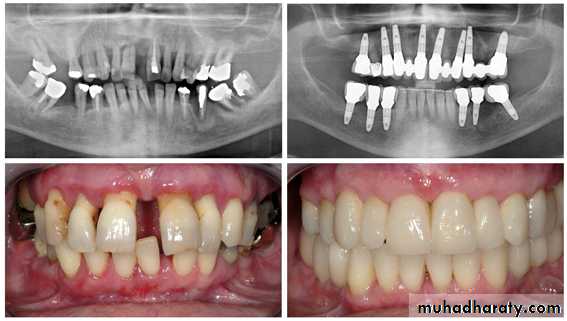

Corrective orthodonticsIt employs certain technical procedures to reduce or correct the malocclusion and to eliminate the possible sequelae of malocclusion.

Types of orthodontic treatment

Surgical orthodonticsSIDE EFFECTS AND COMPLICATIONSHYPOTHETICALLY LINKED TO ORTHODONTICS